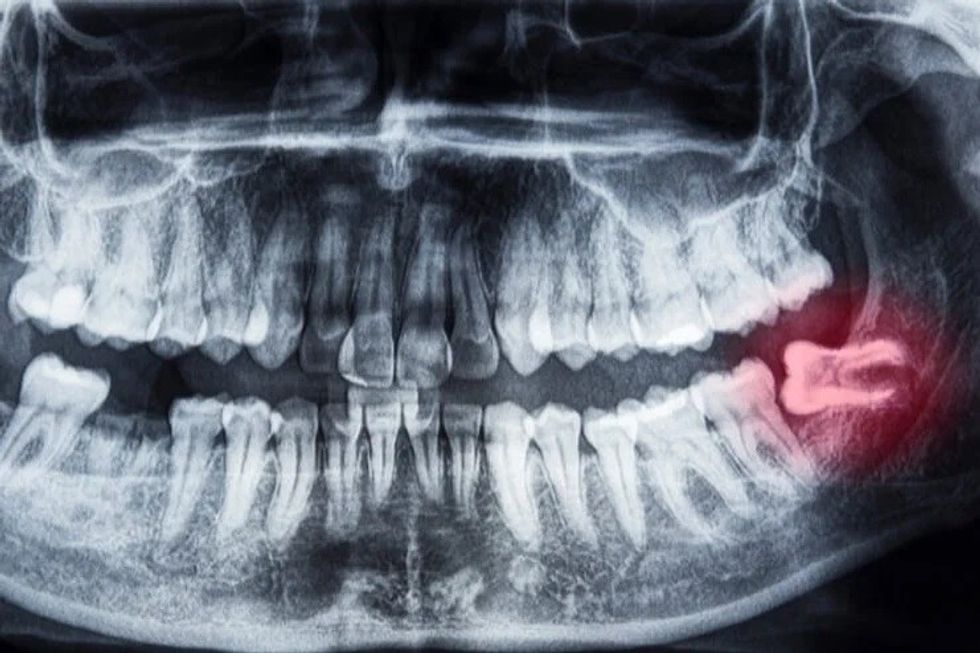

Problemi më i shpeshtë klinik që shohim është perikoroniti, (një infeksion i lokalizuar). Pa hapësirë të mjaftueshme për eruptim të plotë të dhëmbit të pjekurisë, indi i mishit të dhëmbëve rreth dhëmbit të pjekurisë mund të irritohet dhe infektohet, duke rezultuar në dhimbje të përsëritura, ënjtje dhe probleme me përtypjen dhe/ose gëlltitjen.

2. Formimi i lezioneve cistike

Sëmundjet jo-infektive mund të lindin gjithashtu të lidhura me një dhëmb të pjekurisë. Cistet janë ‘balona’ të mbushura me lëng brenda kockës së nofullës që zhvillohen si rezultat i dhëmbëve të prekur dhe zgjerohen ngadalë duke shkatërruar kockën e nofullës dhe herë pas here dhëmbët afër saj. Ato mund të jenë shumë vështirë për t’u trajtuar nëse dhëmbët e pjekurisë nuk hiqen në vitet e adoleshencës.

4. Dëmtimi i dhëmbëve ngjitur

Nëse nuk ka hapësirë të mjaftueshme për të pastruar rreth dhëmbit të pjekurisë, dhëmbi që gjendet para tij, molari i dytë, mund të ndikohet negativisht duke rezultuar në sëmundje të mishrave të dhëmbëve, humbje kockash rreth dhëmbit dhe/ose prishje.